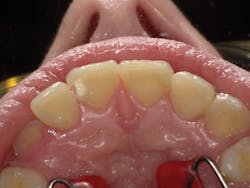

Figure 1

I'll demonstrate this material's versatility with a few cases. First is a large Class III cavity. The patient was extremely apprehensive, so we decided to prepare the cavity using the Lite Touch (AMD Lasers) erbium YAG laser. Very often, as in this case and the next few cases that we will depict, cavity preparation can be performed without anesthetic. In Figure 1, we see the preoperative image of the large Class III cavity on tooth No. 8. Using the Lite Touch laser (figure 2), we were able to excavate the entire cavity in a clean and efficient manner (figure 3). Using a fine diamond, a slight bevel was completed on the enamel at the cavo surface margin. By beveling the enamel, we improve the bond of the adhesive and allow for a seamless blend of the restorative material to the outer tooth structure. In deep restorations such as this, a calcium liner can help minimize sensitivity and act as a buffer between the restoration and pulp. Both Calcimol LC (Voco) and Theracal (Bisco) can be used in this manner. In this case, we decided to use Theracal. Theracal was placed in the deepest area and light-cured for 15 seconds (figure 4). After a 37% phosphoric acid etch of the enamel margin, we applied Futurabond U (Voco) as per the manufacturer's instructions and light-cured for 10 seconds. Admira Fusion shade A2 was placed in three increments and polished. The final restoration exhibits a beautiful luster and a seamless blend from the restoration to the natural tooth (figure 5).